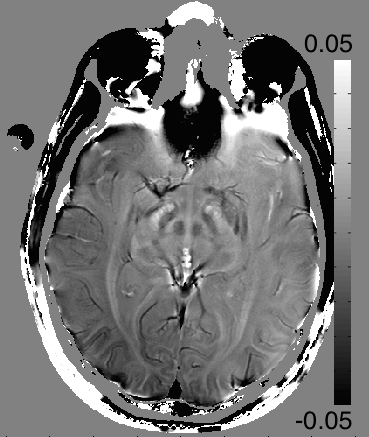

Refer to caption

(a) Magnitude of 1st echo

(b) PPM map, 𝚽𝚽\bf\Phi

(c) Corrected PPM map,𝚽𝐡subscript𝚽𝐡{\bf\Phi_{h}}

(d) PPM map of the estimated background, 𝚽𝐛=𝚽𝚽𝐡subscript𝚽𝐛𝚽subscript𝚽𝐡{\bf\Phi_{b}}={\bf\Phi}-{\bf\Phi_{h}}

Figure 5: Background suppression of a ppm map in a healthy volunteer. (a): Magnitude of the first echo of a multi echo sequence. (b): PRF map estimation using ARMA technique.(c): Background suppressed PRF map. Blood vessels appear darker due to magnetic susceptibility effects. (d): Estimated background field map in ppm.

Figure 5 shows brain data, acquired using a 3T scanner (MR750; GE Healthcare Technologies, Waukesha, WI) from a healthy volunteer, using a 2D-MFGRE sequence with echo spacing = 3.4ms, number of echoes = 16, TE = 2.4 to 28.5 ms, TR = 2200 ms, flip = 60, FOV = 22cm, matrix = 320x256, slice thickness = 5mm, number of slices = 30. An ASSET calibration scan is performed, and sensitivity maps for each of the 32 coils in a 32-channel head coil are obtained. K-space is under-sampled by a factor of 2 by skipping every other frequency encoding line. The magnitude of the first echo is shown in panel (a). The reconstructed images are processed pixel wise by fitting a infinite impulse response (IIR) filter to each echo train. This was done using the Auto Regressive Moving Average (ARMA) [27] technique. The PRF of the dominant peak can be extracted from the coefficients of the IIR filter. The resulting PRF in ppm at each pixel is illustrated in Panel (b). Panel (c) shows the background corrected image. Blood vessels appear darker due to a negative ppm shift of oxidized blood. Brain structures in the mid brain also show significant contrast after applying our background suppression technique. Panel (d) shows the difference of (c) and (b), i.e. the suppressed background. Off resonance shifts can be seen in particular near air cavities near the sinus and the ears. This example demonstrates the potential of the method for quantitive estimation of PRF shifts due to magnetic susceptibility differences for different tissue types.